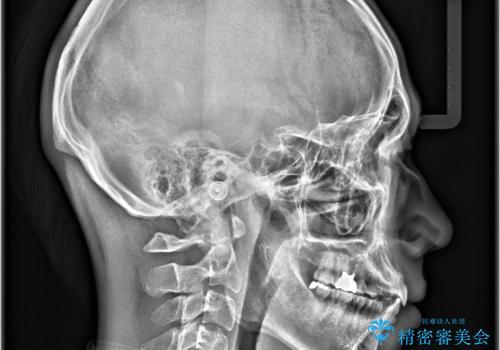

- 主訴:上下前歯の凸凹を治したい、下の前歯が見えないのも改善したい

叢生の改善、前歯被蓋量の改善、顔に対しての正中の改善をインビザラインにて行いました。

モデレートパッケージは作製可能枚数26枚という枚数制限があるため、臼歯部はあまり大きな動きはしない設計にしています。

正中を合わせるため、マウスピースの装着とともに顎間ゴムも使用していただきました。

治療期間:12か月

リファイメント回数:2回